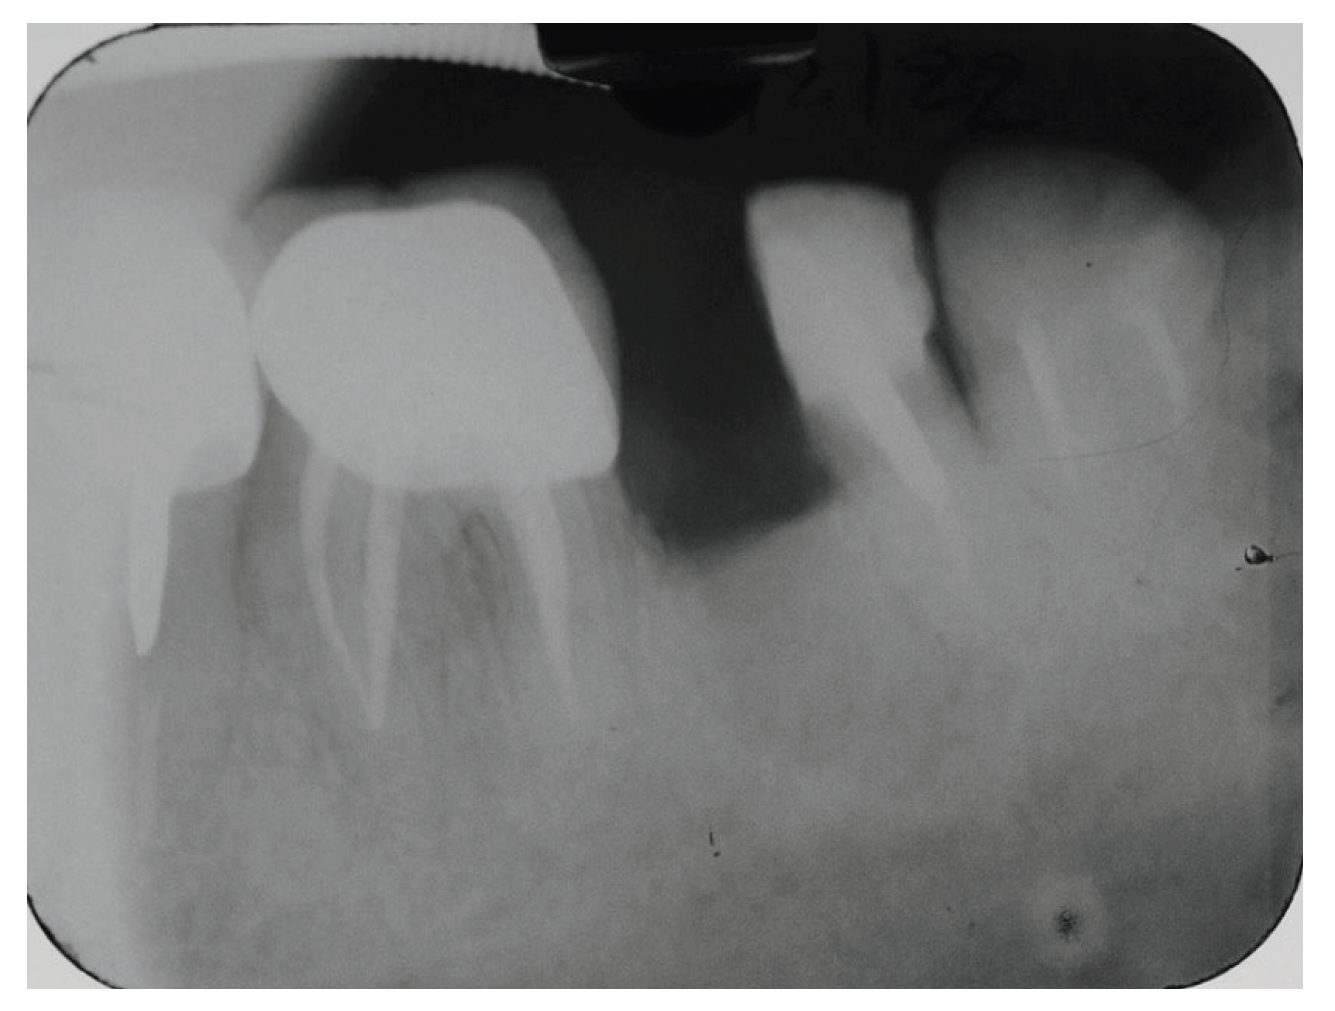

A periapical radiograph in the molar region of #46-47 teeth revealed that there was a radiolucent area in the middle third of the mesial root of tooth #47. This lesion was located mesially and it seems to be rather well defined in this area but coronally the bone loss had a J-shape appearance. In addition, subgingival carries in the distal roots of #47 and #46 were also detected (Figure 2). Both teeth had been restored with cast posts and splinted fused to metal ceramic crowns. Crestal bone between the two teeth appeared to be moderately resorbed.

Based on the clinical and the radiographic findings, a root fracture of the mesial root of tooth #47 was suspected while the prognosis of both teeth were evaluated as unfavourable due to the presence of caries, the extensive restorations and the minimal remaining tooth structure.

Figure 2. Periapical X-Ray of #46, #47.